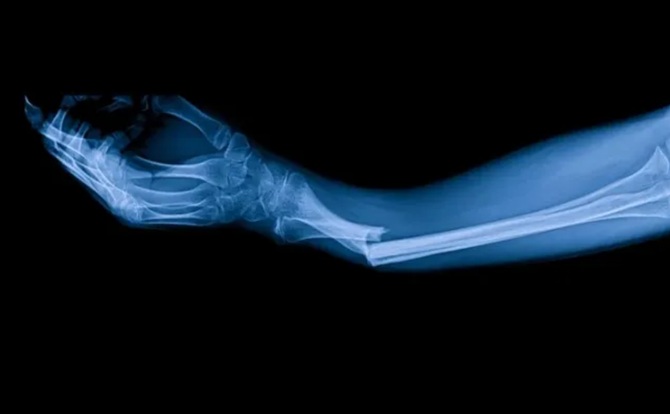

В одному з експериментів пацієнт з переломом зап’ястя отримав ін’єкцію через невеликий розріз довжиною всього 3 см. Вже через три хвилини кістка відновилася, тоді як стандартне хірургічне втручання потребувало б встановлення металевої конструкції та подальшої повторної операції з її видалення. Через три місяці після процедури кістка зросла повністю і без ускладнень. Це лише один із численних успішних прикладів застосування Bone-02.